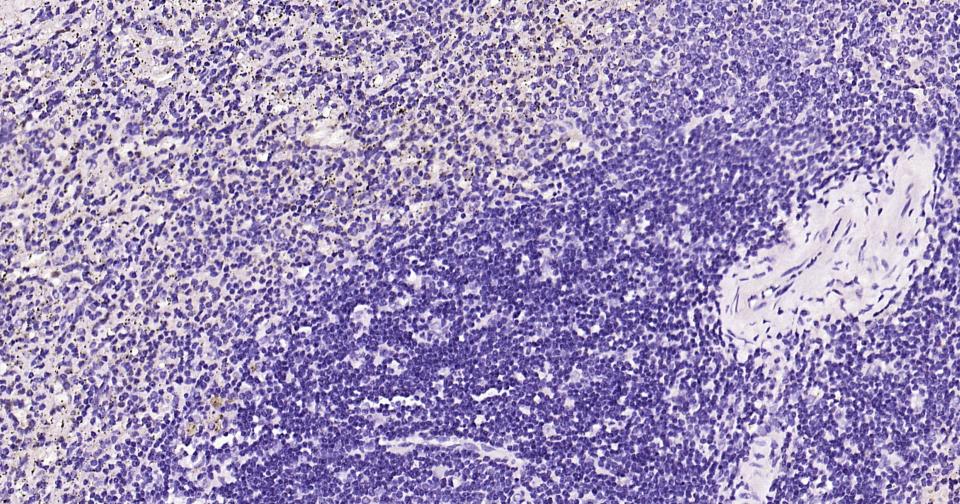

(Negative control) Paraformaldehyde-fixed, paraffin embedded Human Spleen; Antigen retrieval by boiling in sodium citrate buffer (pH6.0) for 15 min; Antibody incubation with MBP Monoclonal Antibody, Unconjugated(bsm-61377R) at 1:200 overnight at 4°C, followed by conjugation to the bs-0295G-HRP and DAB (C-0010) staining and DAB (C-0010) staining.